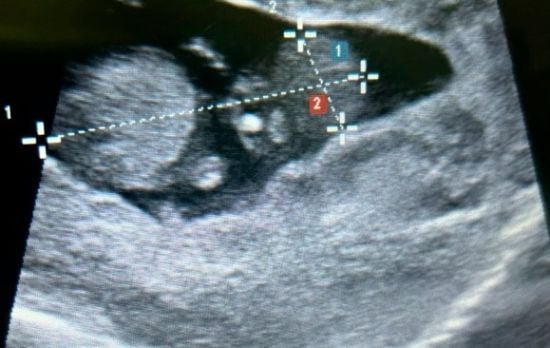

У жінки сталася вкрай рідкісна позаматкова вагітність у печінці – фотоВід / 01.10.2024 Вона дізналася про це на шостому тижні вагітності.